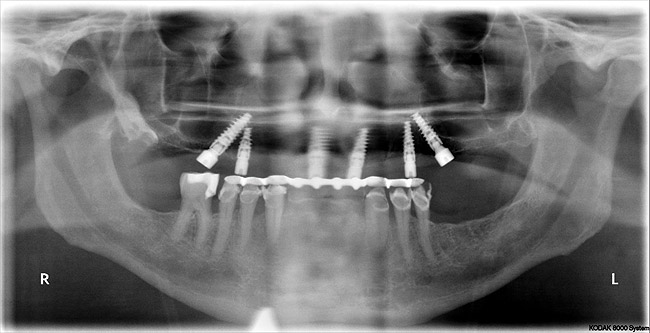

Figure 6  Postoperative panorex, “all-on-six” patient in Figure 5. Note proximity of angled posterior implants to anterior wall of maxillary sinuses. Surgery performed flaplessly.

Figure 6